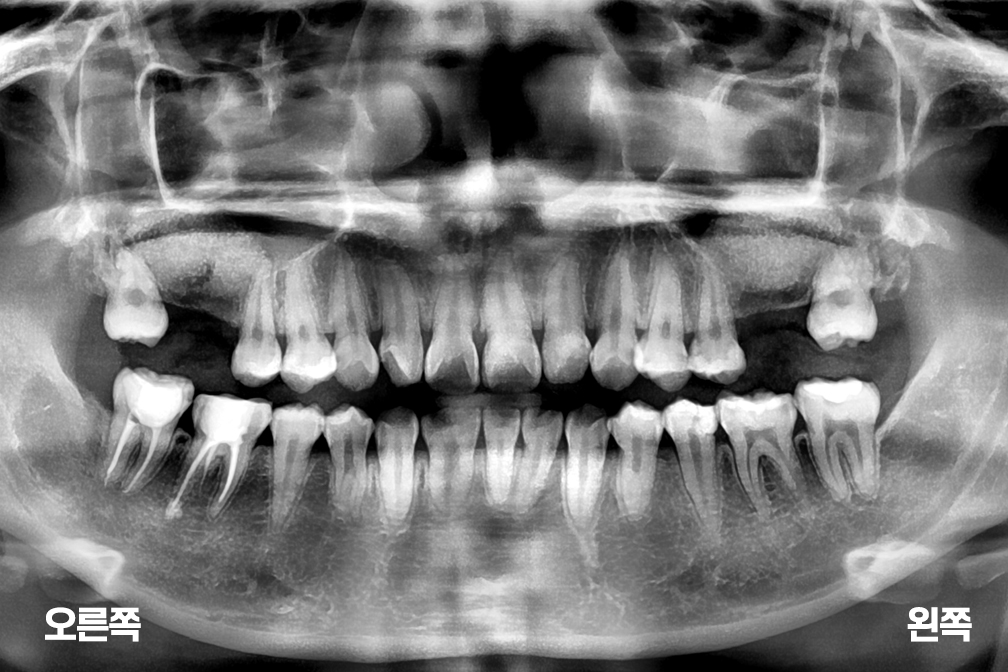

상악동거상술

위 전후사진은 이미지사진으로 실제 눈으로 보는 것과는 다를 수 있으며, 환자의 치아상태과 방법에 따라 치료결과가 다를수 있습니다.

사진의 날짜는 촬영날짜이며 치료의 기간이 아님을 알려드립니다.

치료 후 치아표면의 탈회 , 충치, 치근흡수 등의 부작용이 있을 수 있습니다.